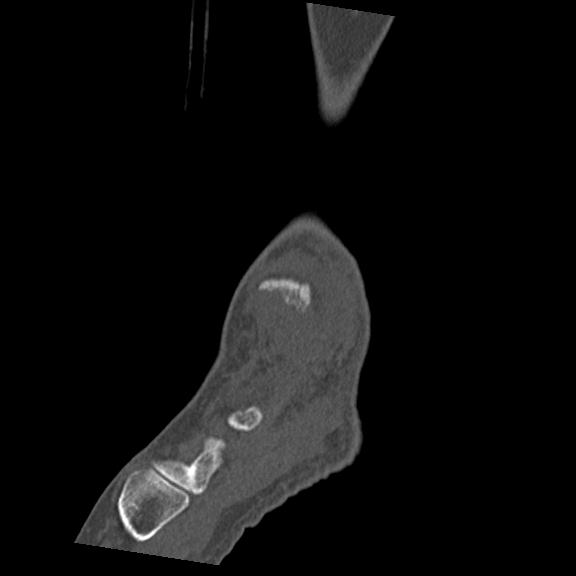

56476 8/28 4R 1/21 2R 左足関節 デジカメ写真 72歳女性 右足関節AS